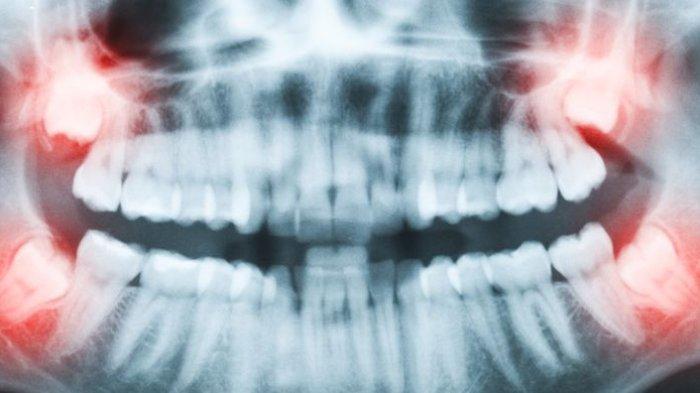

TRIBUNHEALTH.COM - Gigi impaksi merupakan kondisi dimana gigi tidak tumbuh secara sempurna.

Biasanya kondisi ini disebabkan karena kurangnya ruang untuk gigi tumbuh.

Kurangnya ruang untuk gigi tumbuh akan menyebabkan gigi yang akan tumbuh tertahan oleh gigi lainnya.

Gigi yang paling sering mengalami impaksi adalah gigi bungsu.

Namun gigi impaksi juga bisa terjadi pada gigi mana saja.

"Dengan kondisi tersebut, biasanya kita mengambil kesimpulan lebih awal. Bahkan biasanya kalau pasien saya pada gigi geraham tiga bila ada kelihatan atau secara rontgen foto ada tanda bahwa kemungkinan gigi ini mengalami impaksi, saya justru anjurkan pasien untuk dilakukan tindakan lebih awal tanpa menunggu harus ada keluhan dahulu," ucapnya.